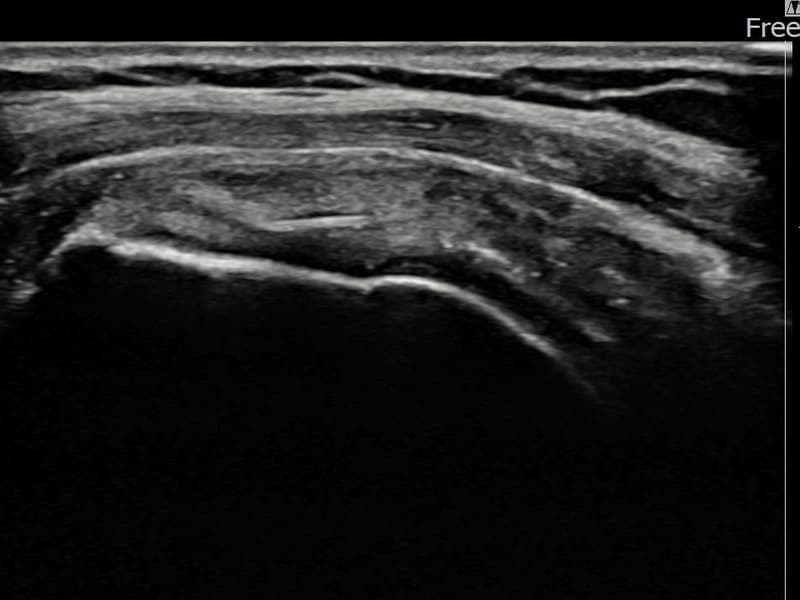

시술 전 초음파 측정 결과 파열 크기는 5mm × 3mm (힘줄 두께의 약 25% 결손)로 확인되었습니다. 시술 전 초음파에서 좌측 극상근건 부착부의 에코 단절과 힘줄 결손 소견이 확인되었습니다. 시술 후 초음파에서 부착부 연속성이 회복되고 결손 부위에 재생 조직이 형성된 것이 관찰되었습니다.

50대 후반 여성 환자분으로, 왼쪽 어깨 부착부 통증이 지속되어 내원하셨습니다. 야간 통증이 심해 수면이 어렵고, 팔을 들어 올릴 때 날카로운 통증이 있어 일상 생활에 많은 불편함이 있으셨습니다. 초음파 검사에서 좌측 극상근건 부착부 부분파열이 확인되었으며, 초음파 유도 하 축소봉합술을 시행하였습니다. 시술 후 보조기 착용과 재활 운동을 통해 꾸준히 회복하였고, 시술 14주 후 추적 초음파에서 부착부 힘줄 연속성이 완전히 회복된 것이 확인되어 야간 통증이 소실되고 정상 수면이 가능해지셨습니다.